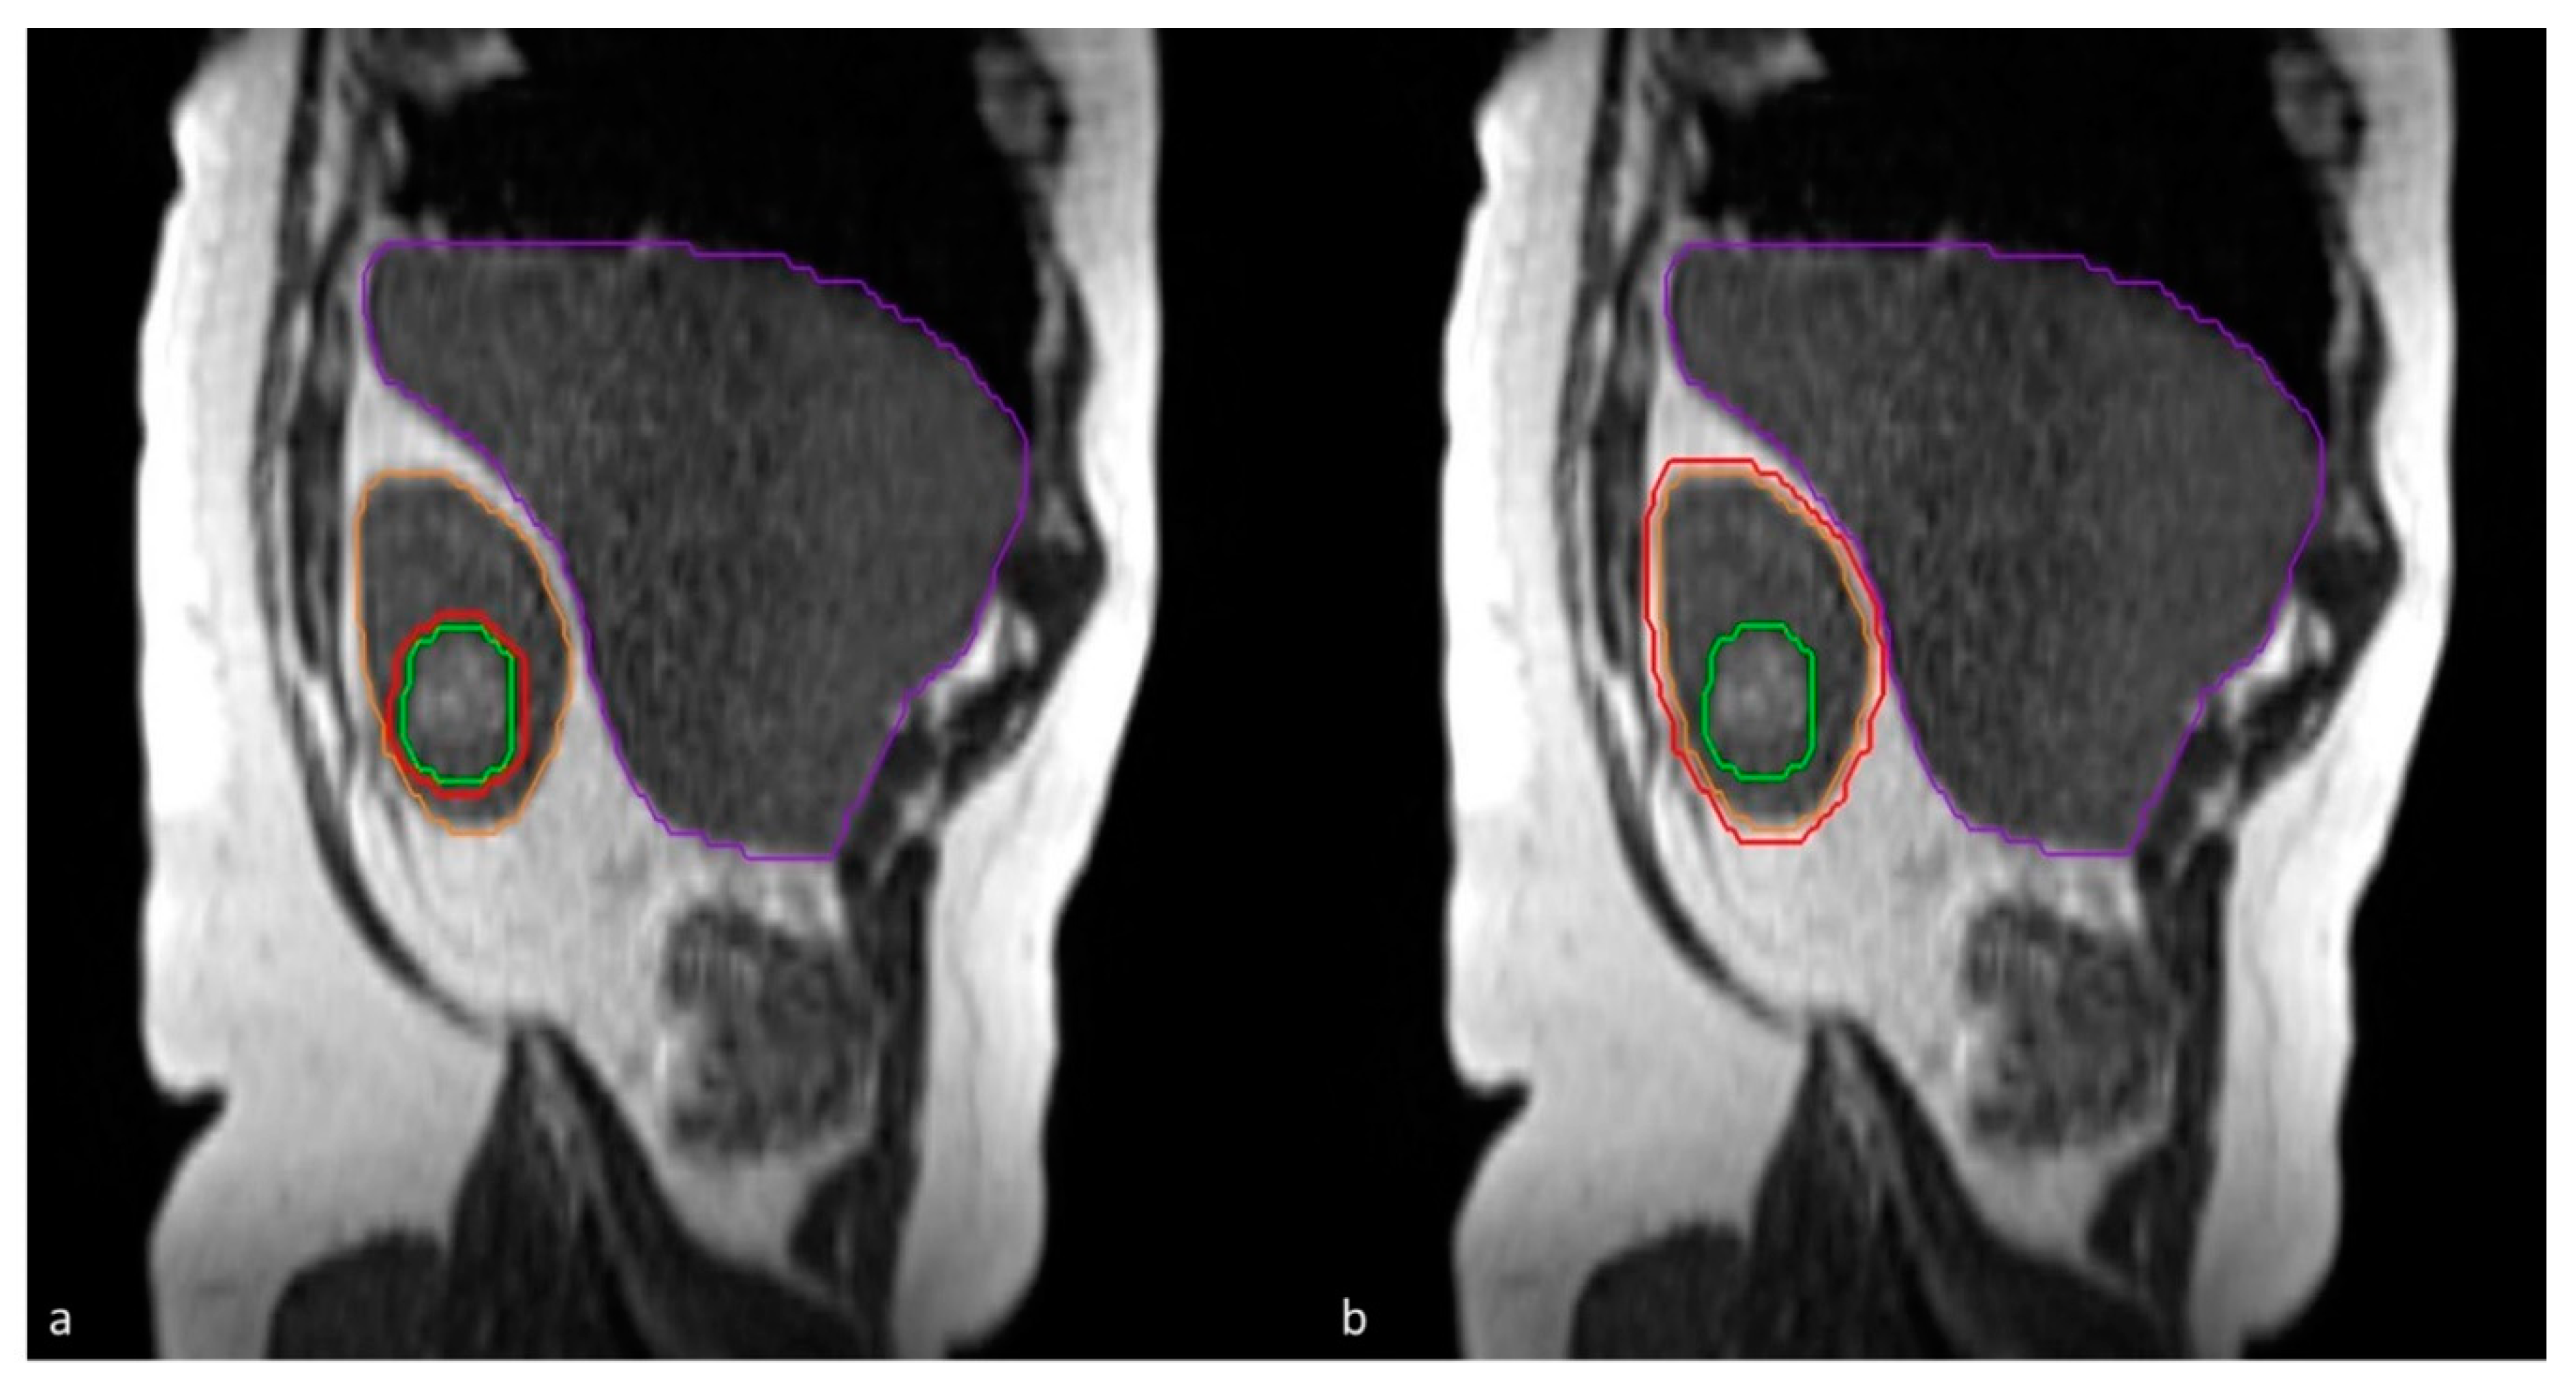

3.2. The Need for Daily Plan Re-Optimization